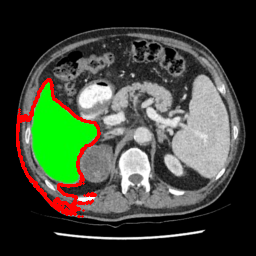

| U-Net | nnU-Net | TransU-Net | SAM-PP-0 | SAM-PP-5 |

| SAM-PP-50 | SAM-PP-100 | SAM-Mix-5 | SAM-Mix-50 | SAM-Mix-100 |

Our primary findings comparing the proposed model to baseline fully-supervised models when segmenting the liver from the LiTS dataset are reported in Table 1. The reported results demonstrate that our SAM-Mix model consistently achieves higher Dice scores compared to the fully supervised baselines as well as the two-stage SAM-PP method. Against U-Net, the best-performing fully supervised method, the SAM-Mix variant trained on 50 segmentation labeled slices (SAM-Mix-50), achieves a Dice score improvement of 5.9%. In terms of Hausdorff distance, while the fully-supervised baselines do slightly outperform SAM-Mix-5 and SAM-Mix-100, SAM-Mix-50 does achieve a lower Hausdorff distance by 22.38%. Qualitative evaluation as shown in Figs. 3 further affirms the superiority of SAM-Mix over baseline and existing fully-supervised methods as well as the two-stage SAM-PP variants. Furthermore, the boxplot visualization in Fig. 2 showcases consistently improved performance by SAM-Mix outperforming all the fully supervised and semi-supervised methods.